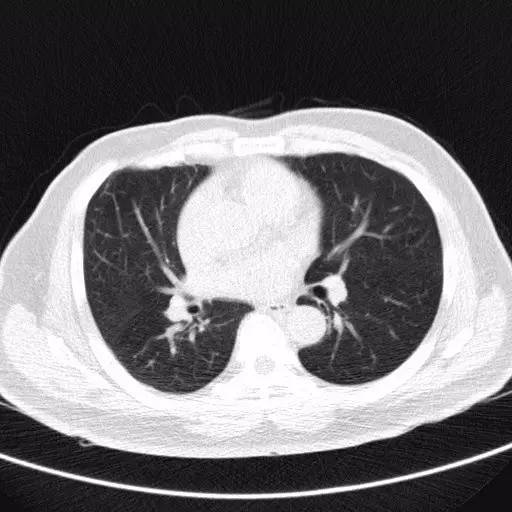

胸部CT

CT比胸片具有更高的灵敏度和特异度,能够显示小结节的二维形态,还能清晰显示小结节周围组织的影像学特点。胸部CT扫描不仅能够更清晰的观察肺部小结节的形态及大小,还能通过不同时间的CT图像动态的比较小结节的变化情况。胸部薄层CT具有更高的分辨率,应该作为评估肺部孤立性小结节性质的首选影像学检查方法。

低剂量螺旋CT

欧美和日本自90年代后以低剂量螺旋CT(LDCT)为主要检查方法的大型普查项目均显示肺癌筛查恶性检出率在1%~2%,早期肺癌检出率80%以上,5年甚至10年生存率达80%以上,预期10年生存率可达88%。所有研究数据均表明通过筛查可以改善肺癌病人的生存。目前LDCT技术上日趋成熟,扫描辐射剂量约为2.0mSV,明显低于常规CT,是最有效的肺癌筛查手段。

应该每年进行一次低剂量螺旋CT筛查,如发现肺内病变,应在专业医师建议下进一步查胸部薄层CT或胸部增强CT。